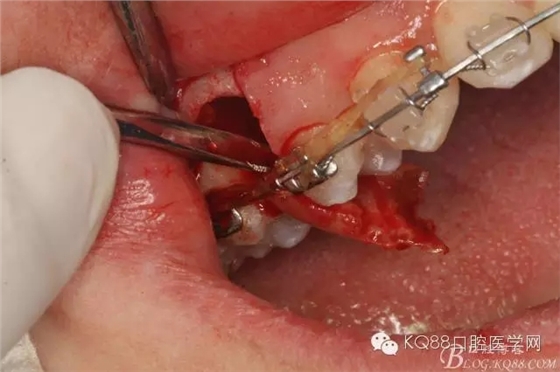

圖13. 用小球鉆去除約1mm牙槽骨,暴露15牙根面約5mm。

圖14.用小球鉆縱分15牙根

圖15 .微創(chuàng)挺把15牙根縱分成近遠(yuǎn)中兩塊